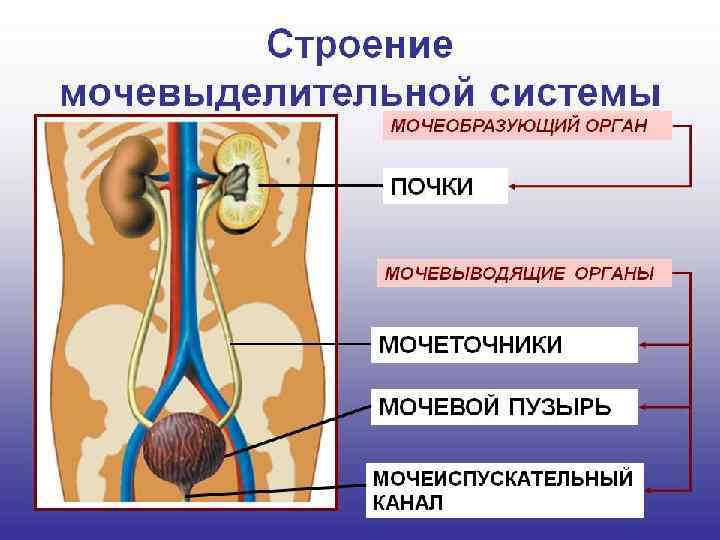

ПОЧКА (ren, греч. nephros) - парный кскреторный орган красно-бурого цвета, образующий и выводящий мочу. Размеры: длина 10 -12 см; ширина 5 -6 см; толщина 4 см. Масса 120 -200 г

ПОЧКА (ren, греч. nephros) - парный кскреторный орган красно-бурого цвета, образующий и выводящий мочу. Размеры: длина 10 -12 см; ширина 5 -6 см; толщина 4 см. Масса 120 -200 г